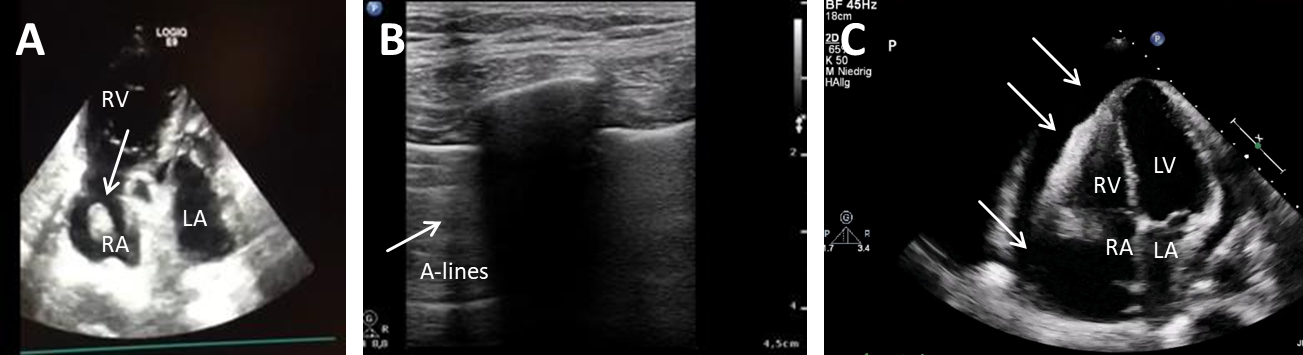

Etiologically, obstructive shock is caused by an impaired diastolic filling and thus a reduced cardiac RV- or LV-preload (venous return). A reduced preload is caused by tension pneumothorax, V. cava compression syndrome, mediastinal tumors, pericardial effusion or ventilation with a very high PEEP level. On the other hand, diseases which lead to an increased afterload and thus cardiac output may lead to obstructive shock. Causes associated with an increase in afterload are, for example, an aortic dissection, pulmonary embolism or Leriche syndrome. A pulmonary embolism or mediastinal space-occupying mass increases right-ventricular afterload, while decreasing left ventricular preload. The same mechanisms may occur in case of obstructive intracardial mass as displayed in Fig. 1, (Ref. [12]). Obstruction of the aortic blood flow however increases left ventricular afterload (e.g., Leriche syndrome [aortoiliac occlusive disease], aortic dissection) [13].

Fig. 1.Transversal (A,B) and coronal (C) reconstructions of a computed tomography (CT) angiography shwoeing a rare cause for obstructive shock. (A) Tumor mass (TU) infiltrating the right ventricular wall and left ventricular ouitflow tract. (B) The tumor (TU) mass compresses the right artrium (RA) and right ventricle (RV). The tumor has no direct contact to the left ventricle (LV). (C) Demonstrates tumor grophs along the right heart in coronal reconstruction. Adapted from [12].